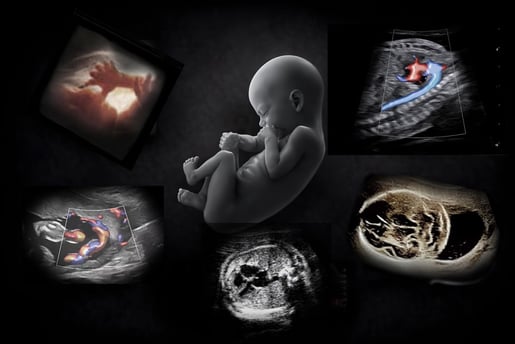

Free OB Ultrasound

The most powerful technology in medicine

is the person using it.